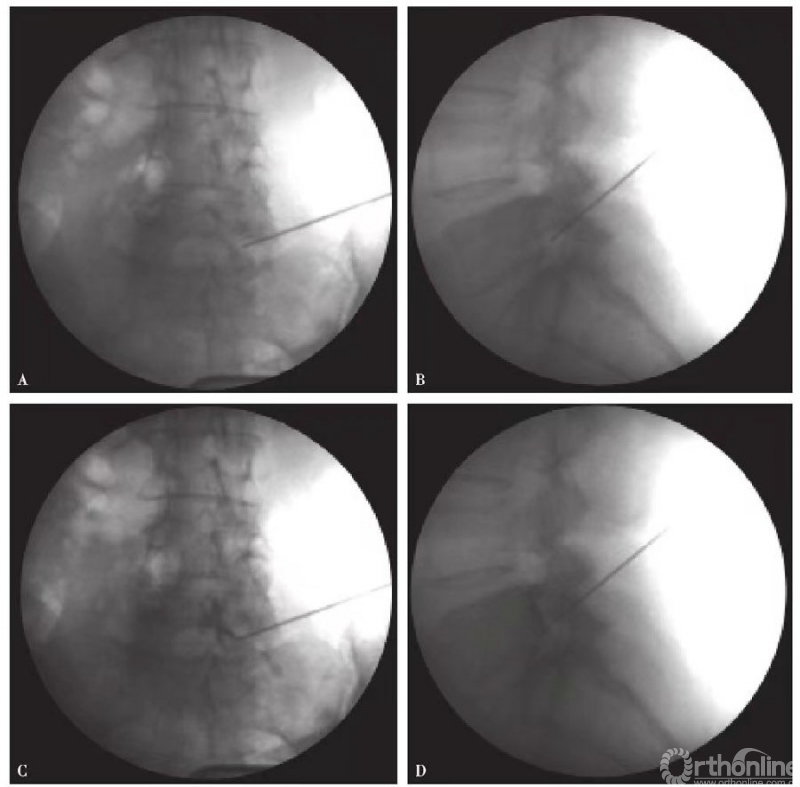

(1)6号或者9号腰椎穿刺针,透视下穿刺至神经根出口区(图1):

图1 穿刺示意图 A.冠状位中线旁开约4cm,平横突下沿进针,向内偏20°;B.矢状位上平横突下沿进针,向下偏约20°(图片引用自:Tajima T, Furukawa K,Kuramochi E.Selective lumbosacral radiculography and block.Spine,1980,5(1):68-77)

1)正位影像:相应椎体椎弓根下缘中点,下位椎体上关节上缘;

2)侧位影像:侧位椎间孔后缘1/3;

3)S1在第一骶神经孔;

4)准确穿刺到神经根,会诱发出神经根相应支配区域的放射痛,并术中询问患者是否能够复制术前下肢症状;

图2 选择性腰5神经根造影 A、B.穿刺成功正侧位片;C、D.造影后正侧位片

图3 选择性L3神经根造影 A、B.穿刺成功正侧位片;C、D.造影后正侧位片